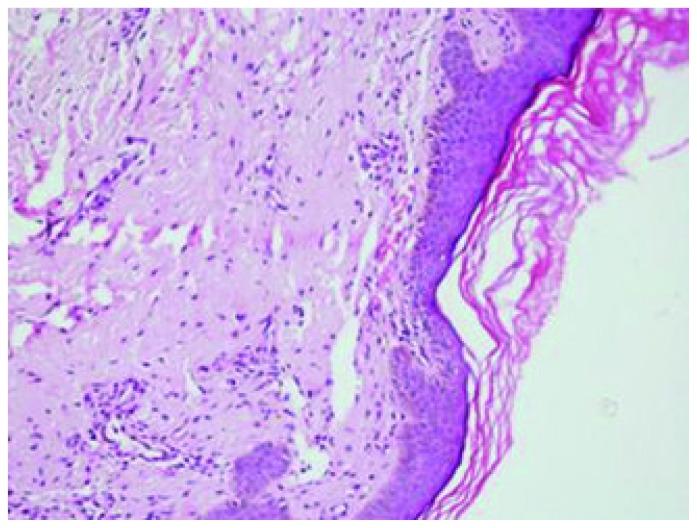

Primary systemic amyloidosis is a rare disease. It primarily involves kidney, heart, peripheral nerves and liver. Intracutaneous hemorrhage manifesting in the form of petechiae, purpura and ecchymoses due to infiltration of blood vessel walls by amyloid deposits are the most common skin lesions. We report a case of primary systemic amyloidosis with multiple, non-itchy, papular lesions in lower eyelids and lower chest wall bilaterally. Diagnosis was confirmed in this case by biopsy of skin lesions using congo red staining. Papular eruptions as seen in index patient are relatively uncommon form of skin manifestations.

原发性系统性淀粉样变是一种罕见的疾病。它主要累及肾脏、心脏、周围神经和肝脏。由于血管壁被淀粉样沉积物浸润,导致皮肤出现瘀点、瘀斑和血肿,这是最常见的皮肤病变。我们报告了一例原发性系统性淀粉样变患者,其双侧下眼睑和下胸部壁有多个、非瘙痒性、丘疹样病变。通过刚果红染色对皮肤病变进行活检,在本例中确诊了诊断。丘疹性发疹在该患者中所见的形式相对较为罕见的皮肤表现形式。